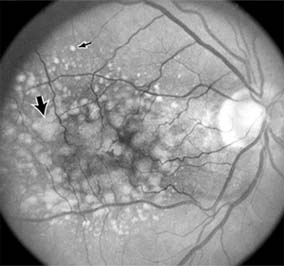

Central serous chorioretinopathy is characterized by serous detachment of the sensory retina as a consequence of focal leakage of fluid from the choriocapillaris through a defect in the retinal pigment epithelium (Figures 10-2 and 10-3). This disease typically affects young to middle-aged men and may be related to life stress events. Most patients present with the sudden onset of blurred vision, micropsia, metamorphopsia, and central scotoma. Visual acuity is often only moderately decreased and may be improved to near-normal with a small hyperopic correction.

Figure 10-2

Figure 10-2: Central serous chorioretinopathy with sensory retinal detachment (arrows) extending into the fovea.

Figure 10-3

Figure 10-3: Fluorescein angiogram of central serous chorioretinopathy shows active disease with both a retinal pigment epithelial detachment (small arrows) and a sensory retinal detachment (large arrows). Two foci of inactive disease (open arrows) are also present.